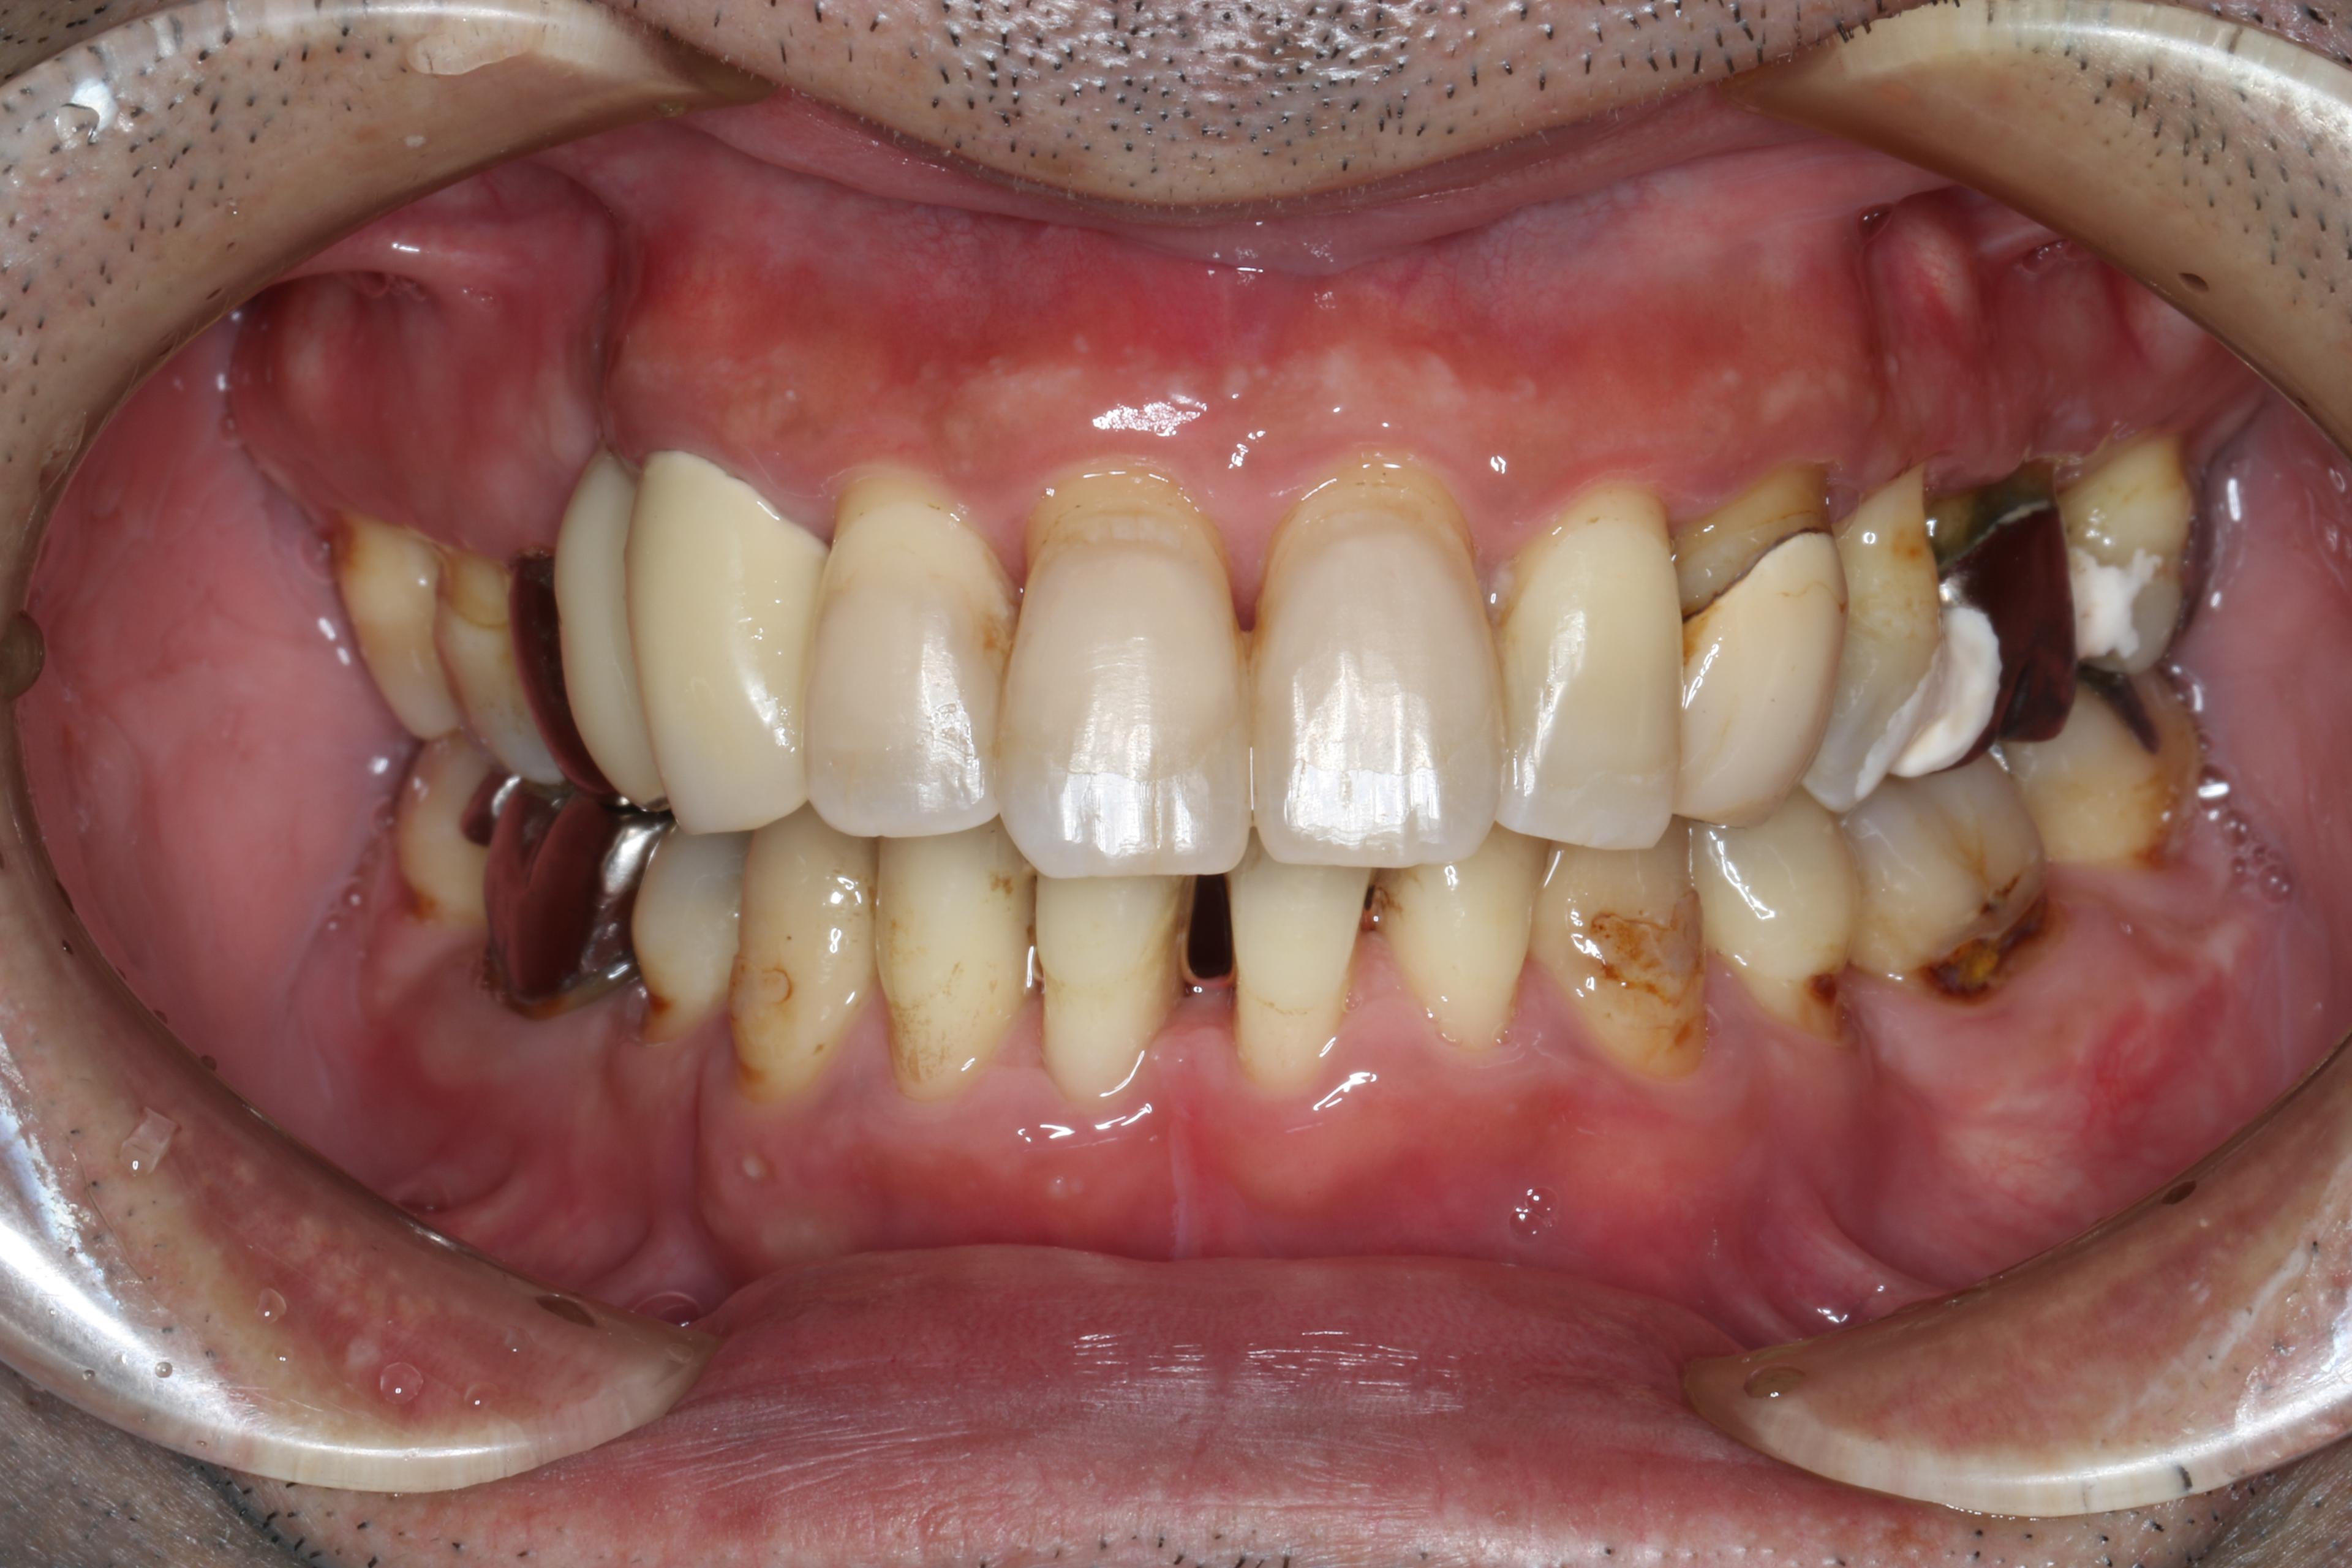

指数病の治療をしたいということでご来院された40代の男性です。写真で分かるとおり歯石がびっしりと着いており歯周炎により歯茎の腫れも相当ある状態でした。

喫煙は1日10本を20年、 糖尿病はありません。

- 広汎型慢性歯周炎 ステージ3 グレードC

と診断をいたしました。